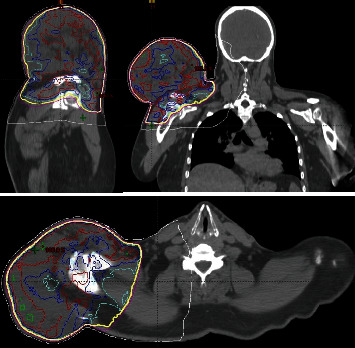

This study examines a unique case of a 61-year-old male with a 5-year history of a progressively growing mass above his right shoulder, diagnosed as a dedifferentiated pleomorphic liposarcoma. Using computerized tomography-guided core needle biopsy, the tumour was identified as intermediate to high grade. Surgical removal required preoperative radiotherapy to reduce the size of the tumour. Several unique characteristics set apart this particular case of liposarcoma: its substantial size, its unpredictable growth pattern, its absence of metastasis, and notably, its prolonged period of being untreated. This case report outlines the clinical background, diagnostic procedures, and treatment modalities employed in managing this condition, emphasizing a localized dual therapy approach combining radiotherapy and surgery. Emphasis is placed on distinguishing liposarcoma from lipoblastoma, a benign adipocyte tumour, to facilitate accurate diagnosis and appropriate treatment selection. The positive result achieved in this case could provide valuable insights for the future treatment and management of similarly sized aggressive tumours.